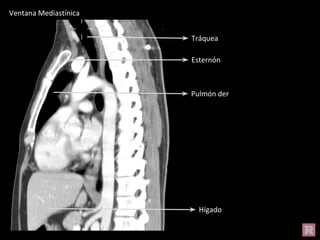

Ventana Mediastínica

Hígado

Tráquea

Esternón

Pulmón der